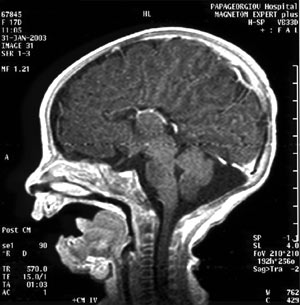

4. Μαγνητική τομογραφία στην περίπτωση 1, που διακρίνεται η απουσία

του μεσολοβίου σε οβελιαία διατομή.

ζώντος τέκνου, Β.Σ. 3410g. Μετά τον τοκετό η προγεννητική διάγνωση της αγενεσίας

του μεσολοβίου επιβεβαιώθηκε με μαγνητική τομογραφία του εγκεφάλου. Στις εικόνες

4 και 5 παρουσιάζεται η απουσία του μεσολοβίου στη μαγνητική τομογραφία σε οβελιαία

και εγκάρσια διατομή αντίστοιχα. Από την παιδιατρική παρακολούθηση, η ψυχοκινητική

ανάπτυξη του παιδιού είναι ικανοποιητική, το ηλεκτροεγκεφαλογράφημα φυσιολογικό,

όπως και τα οπτικά και ακουστικά προκλητά δυναμικά, ενώ και τα αποτελέσματα

της οφθαλμολογικής εξέτασης κινούνταν στα πλαίσια του φυσιολογικού.

Εικόνα

5. Μαγνητική τομογραφία στην περίπτωση 1, που διακρίνεται η απουσία

του μεσολοβίου σε εγκάρσια διατομή.